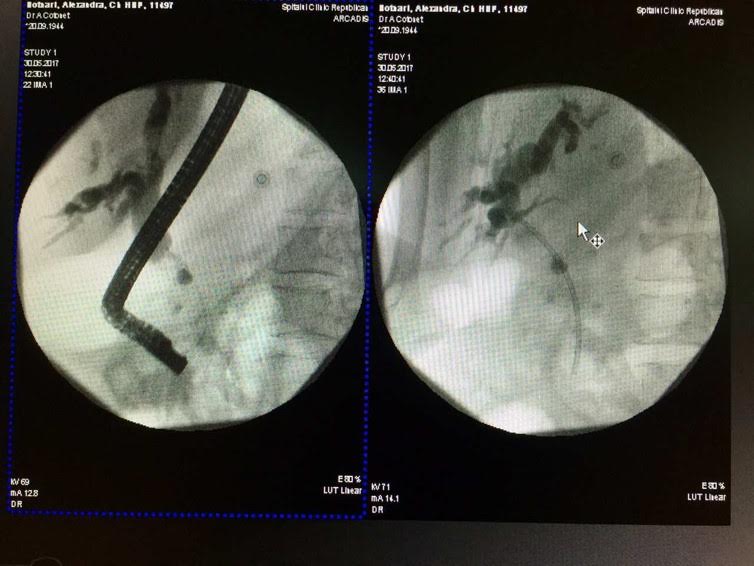

Ulterior, pe 30.05.2017 pacienta a suportat o intervenţie endoscopică miniminvazivă în cabinetul de endochirurgie a SCR. Echipa de chirurgi-endoscopiști formată din d.ș.m. Alic Cotoneţ şi Roman Bodrug, as/m Natalia Râmbu şi anesteziologică - medicul Vasile Roznovan și as/m Natalia Basnari, rezident Vadim Mârca au reuşit protezarea endoscopică a coledocului afectat neoplasic. Datorită condiţiilor moderne de lucru şi experienţei vaste pe care o posedă această echipă, aşa categorie de pacienţi primesc un răgaz confortabil pentru elaborarea conduitei tratamentului, iar gestul chirurgical tradiţional poate fi amânat pentru a fi practicat în condiții de risc minim pentru viaţa bolnavilor.